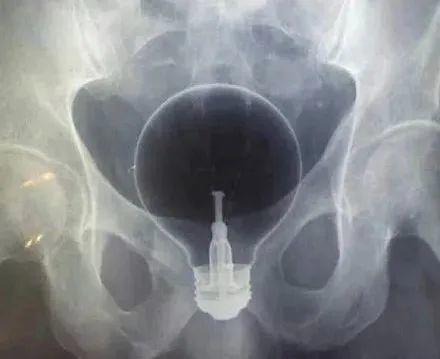

酒瓶、刀、叉子、喷雾罐、哑铃、灯泡、罗非鱼……只有你想不到的,没有“直男”们不敢塞的,比如说,哑铃。